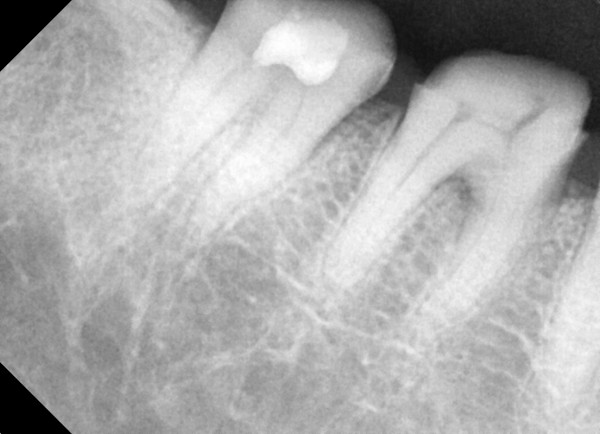

충치치료&신경치료 하루에 끝나는 신경치료

c36d6f431fa4d39e6efca10cb66686a2_1767329674_1678.jpg